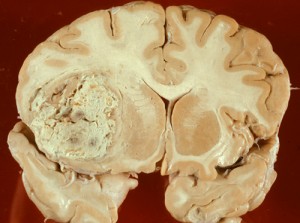

El glioblastoma es un tumor en el cerebro bastante raro y agresivo que generalmente deja muy pocas esperanzas a la persona que lo padece. Este tumor puede aparecer en cualquier edad aunque normalmente se aprecia en las personas que rondan los 55 años. El problema principal es que el glioblastoma casi nunca brinda signos precoces sino que aparece de forma súbita con convulsiones y otros signos neurológicos.